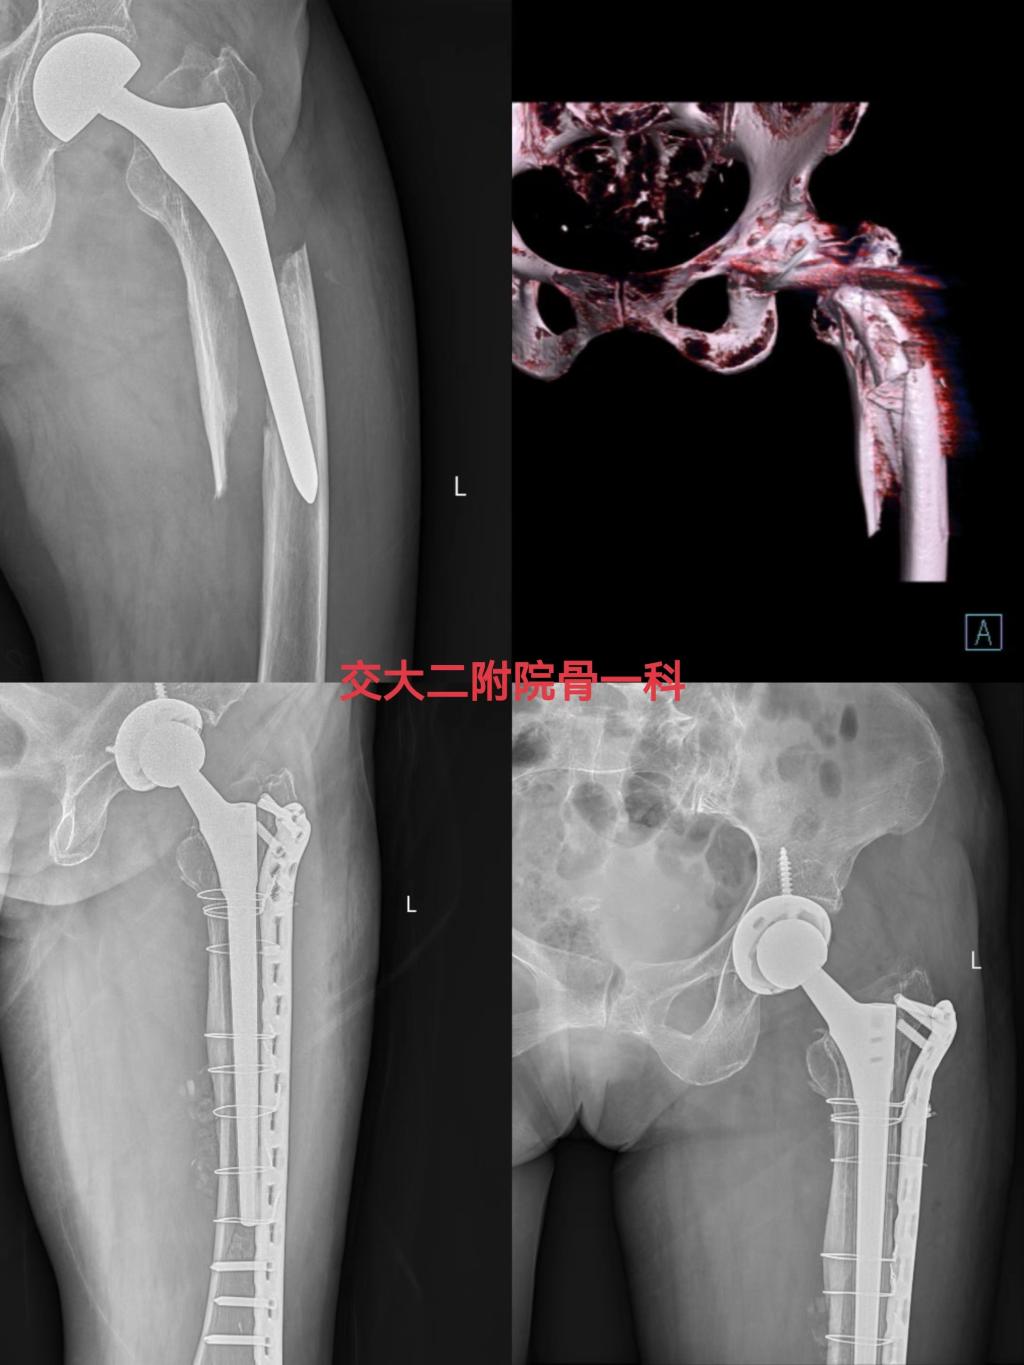

一位女性老年患者因“左人工股骨头置换术后5年,摔伤致左髋部疼痛活动受限3天”诊断入院,诊断为左侧股骨假体周围骨折(VancouverB3型),左侧人工股骨头置换术后,骨质疏松症,完善相关检查排除手术禁忌后,由时志斌副主任主刀完成左髋关节假体翻修手术,术后恢复良好,已顺利出院。